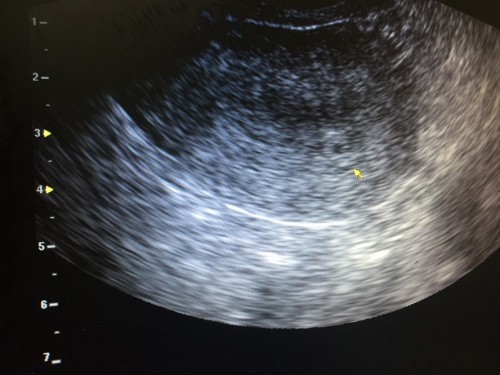

ซาวด์ตอนเดือนนิดๆค่ะ

ใครเห็นเท่านี้บ้างคะตอนเดือนกว่าๆ เครียดคะ ?

Đọc thêm6 วีคค่ะซาวด์วันที่ (4/08/62) เห็นไม่ชัดค่ะ หมอบอกว่าน้องตัวยังเล็กมากเลยไม่ชัด พรุ่งนี้หมอนัดเด๋วได้ซาวด์อีกค่ะ รอซาวด์ใหม่อีกรอบนะคะคุณแม่ เด๋วเห๋นน้องชัดๆค่ะ

4w5d เล็กมากเหมือนกันค่ะ แต่คุณหมอพยายามซูมให้เห็น ซาวด์ผ่านช่องคลอดค่ะ

ไปซาวทางช่องคลอด6w ตัวเล็กแค่ครึ่งเซนแต่เห็นหัวใจตุบๆ ตอน8wเซนครึ่ง

ตอน 6w6dค่ะ ซาวผ่านช่องคลอดค่ะ ถึงจะเห็น ซาวบนหน้าท้องไม่เจอ

ลูกผมซาวตอน 6 สัปดาห์นิดๆ ก้อแค่นี้ เท่าเมล็ดถั่ว